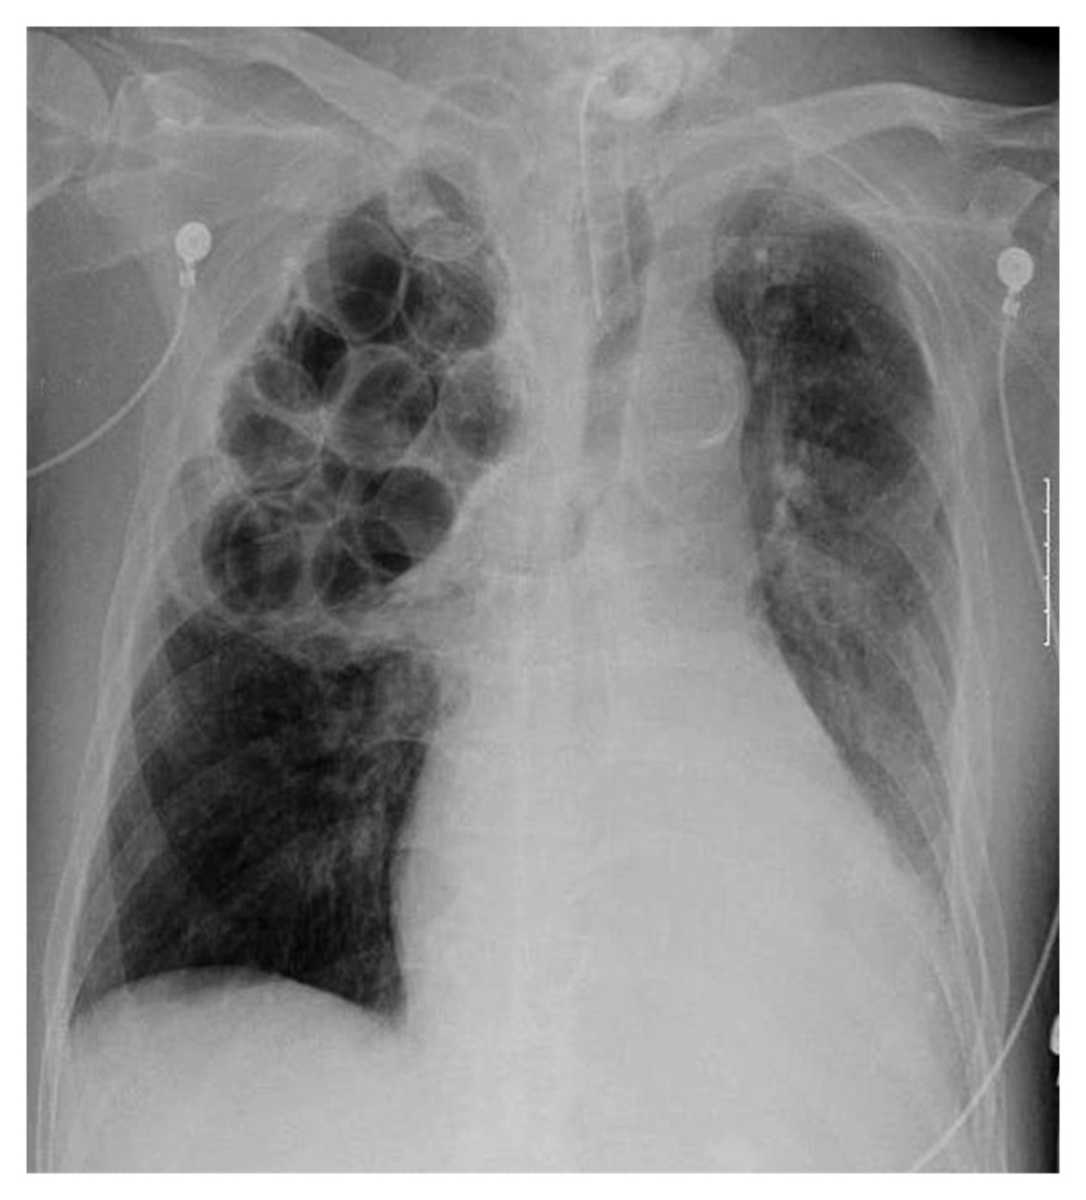

Patient with Repeated Episodes of Septic Shock and History of Pulmonary Tuberculosis in the Past Post category:Spot Diagnosis Post published:December 17, 2021 Share on Facebook Share on X (Twitter) Share on Pinterest Share on Email Share on Reddit An 86-year-old man was hospitalized for repeated episodes of septic shock due to methicillin-resistant Staphylococcus aureus (MRSA) pneumonia. In 1948, the patient had pulmonary tuberculosis. What do you see on this Chest X-ray ? CLICK HERE FOR FULL CASE AND ANSWER Share on Facebook Share on X (Twitter) Share on Pinterest Share on Email Share on Reddit Read more articles Previous PostHyperkeratosis, Papillomatous Plaques, and Loosely Adherent Crust on Legs Next PostErythematous and Irregular Linear Streak Extending from the Hand to the Axilla You Might Also Like Multiple White Lines on the Fingernails June 23, 2021 Patient with Decreased Appetite, Vomiting, Weight Loss and a Mass Through the Umbilicus November 29, 2021 A Diagonal Crease in Each Earlobe September 7, 2021